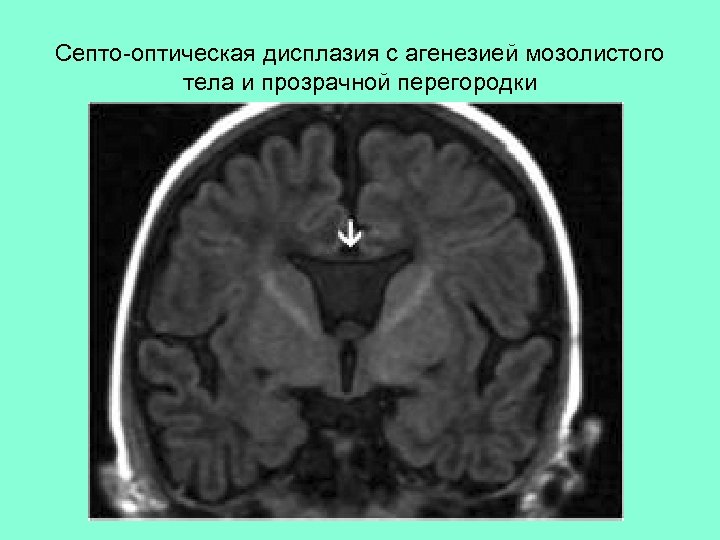

Септо-оптическая дисплазия с агенезией мозолистого тела и прозрачной перегородки